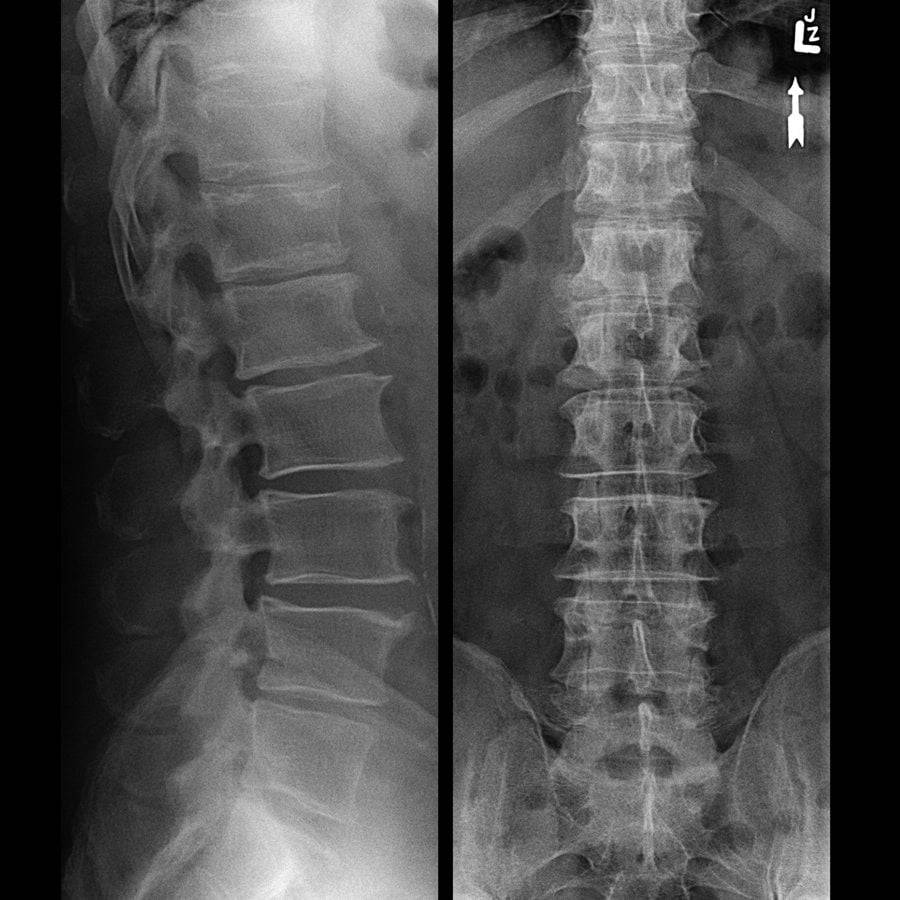

На снимках видно уменьшение щели между позвонками в грудном отделе.